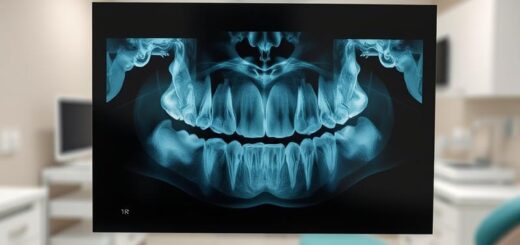

Skaling naddziąsłowy to zabieg, którego celem jest usunięcie kamienia nazębnego znajdującego się powyżej linii dziąseł. Do efektywnego oczyszczenia wykorzystuje się specjalistyczne narzędzia, takie jak skaler ultradźwiękowy. Dzięki temu poprawia się ogólna higiena jamy ustnej. Regularne sesje skalingu naddziąsłowego mają kluczowe znaczenie dla zdrowia zębów, zwłaszcza u osób bardziej podatnych na odkładanie się kamienia.

Skaling poddziąsłowy koncentruje się na eliminacji kamienia, który gromadzi się poniżej linii dziąseł. Jest to niezwykle istotny proces, ponieważ nagromadzenie kamienia w tej strefie może prowadzić do poważniejszych problemów zdrowotnych, takich jak choroby przyzębia czy infekcje. Z mojego doświadczenia wynika, że pacjenci, którzy regularnie korzystają z tego zabiegu, rzadziej skarżą się na bóle związane z podrażnionymi dziąsłami.

Oba rodzaje skalingu odgrywają kluczową rolę w utrzymaniu zdrowych zębów i dziąseł. Ich regularne przeprowadzanie może znacząco obniżyć ryzyko wystąpienia komplikacji związanych z chorobami jamy ustnej. Skaling przyczynia się do zapobiegania gromadzeniu się płytki nazębnej oraz stanom zapalnym dziąseł, co prowadzi do lepszego samopoczucia pacjentów.

Warto pamiętać, że skaling powinien stać się integralną częścią rutynowej opieki stomatologicznej, aby cieszyć się długotrwałymi efektami.